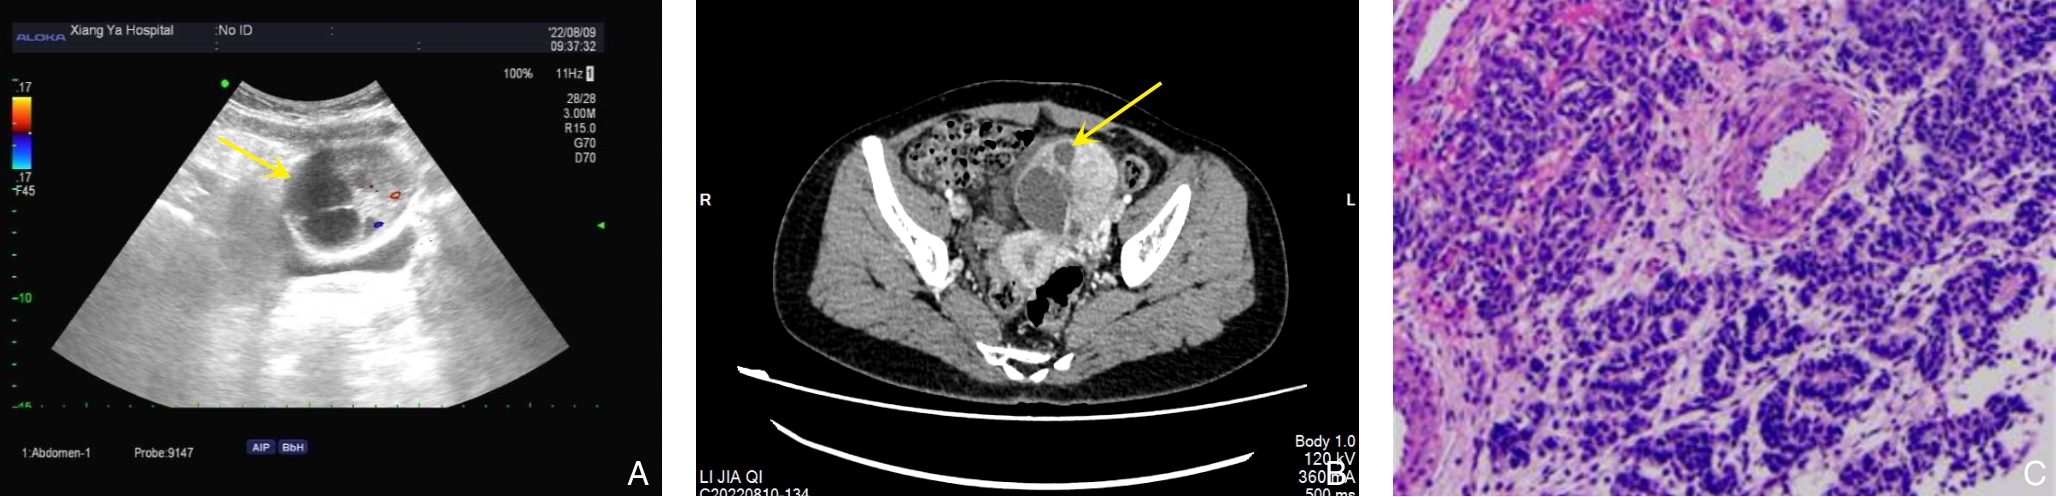

• Occult hepatocellular carcinoma presenting with humeral metastasis as the initial manifestation: a case report and literature review

2026, 35(1):141-148. DOI: 10.7659/j.issn.1005-6947.250622

Abstract (79) HTML (119) PDF 1.24 M (183) Comment (0) Favorites

Abstract:Background and Aims Hepatocellular carcinoma (HCC) presenting initially with bone metastasis is uncommon, and metastasis to the appendicular skeleton is particularly rare. These cases often lack typical liver disease history, elevated alpha-fetoprotein (AFP), or characteristic imaging findings, leading to frequent misdiagnosis or delayed diagnosis. This study reports a rare case of occult HCC presenting with humeral metastasis and reviews the literature to improve clinical recognition and management.Methods The clinical data of a 42-year-old male patient presenting with humeral metastasis as the initial manifestation admitted in August 2025 were retrospectively analyzed, including laboratory tests, multimodal imaging findings, histopathological and immunohistochemical results, treatment, and follow-up outcomes. Relevant literature was also reviewed.Results The patient presented with left shoulder pain. Imaging revealed osteolytic destruction of the left humerus. PET/CT incidentally detected multiple hepatic lesions without significant FDG uptake. Contrast-enhanced ultrasound demonstrated atypical enhancement patterns, initially suggesting a perivascular epithelioid cell tumor. Histopathological and immunohistochemical examination of biopsy specimens from both the humeral and hepatic lesions confirmed moderately differentiated hepatocellular carcinoma with humeral metastasis (CNLC stage IIIb). The patient received systemic therapy with sintilimab plus bevacizumab, followed by transcatheter arterial chemoembolization. After 6 months of follow-up, the intrahepatic lesions had decreased in size, the bone metastasis remained stable, and pain symptoms were significantly relieved.Conclusion HCC presenting with humeral metastasis as the initial manifestation is extremely rare and may lack typical imaging and serological features. Clinicians should consider HCC in patients with unexplained bone metastasis even in the absence of liver disease history or elevated AFP. Multimodal imaging and pathological biopsy are essential for accurate diagnosis and appropriate management.

• 0+1

• 1+1

• 2+1

• 3+1